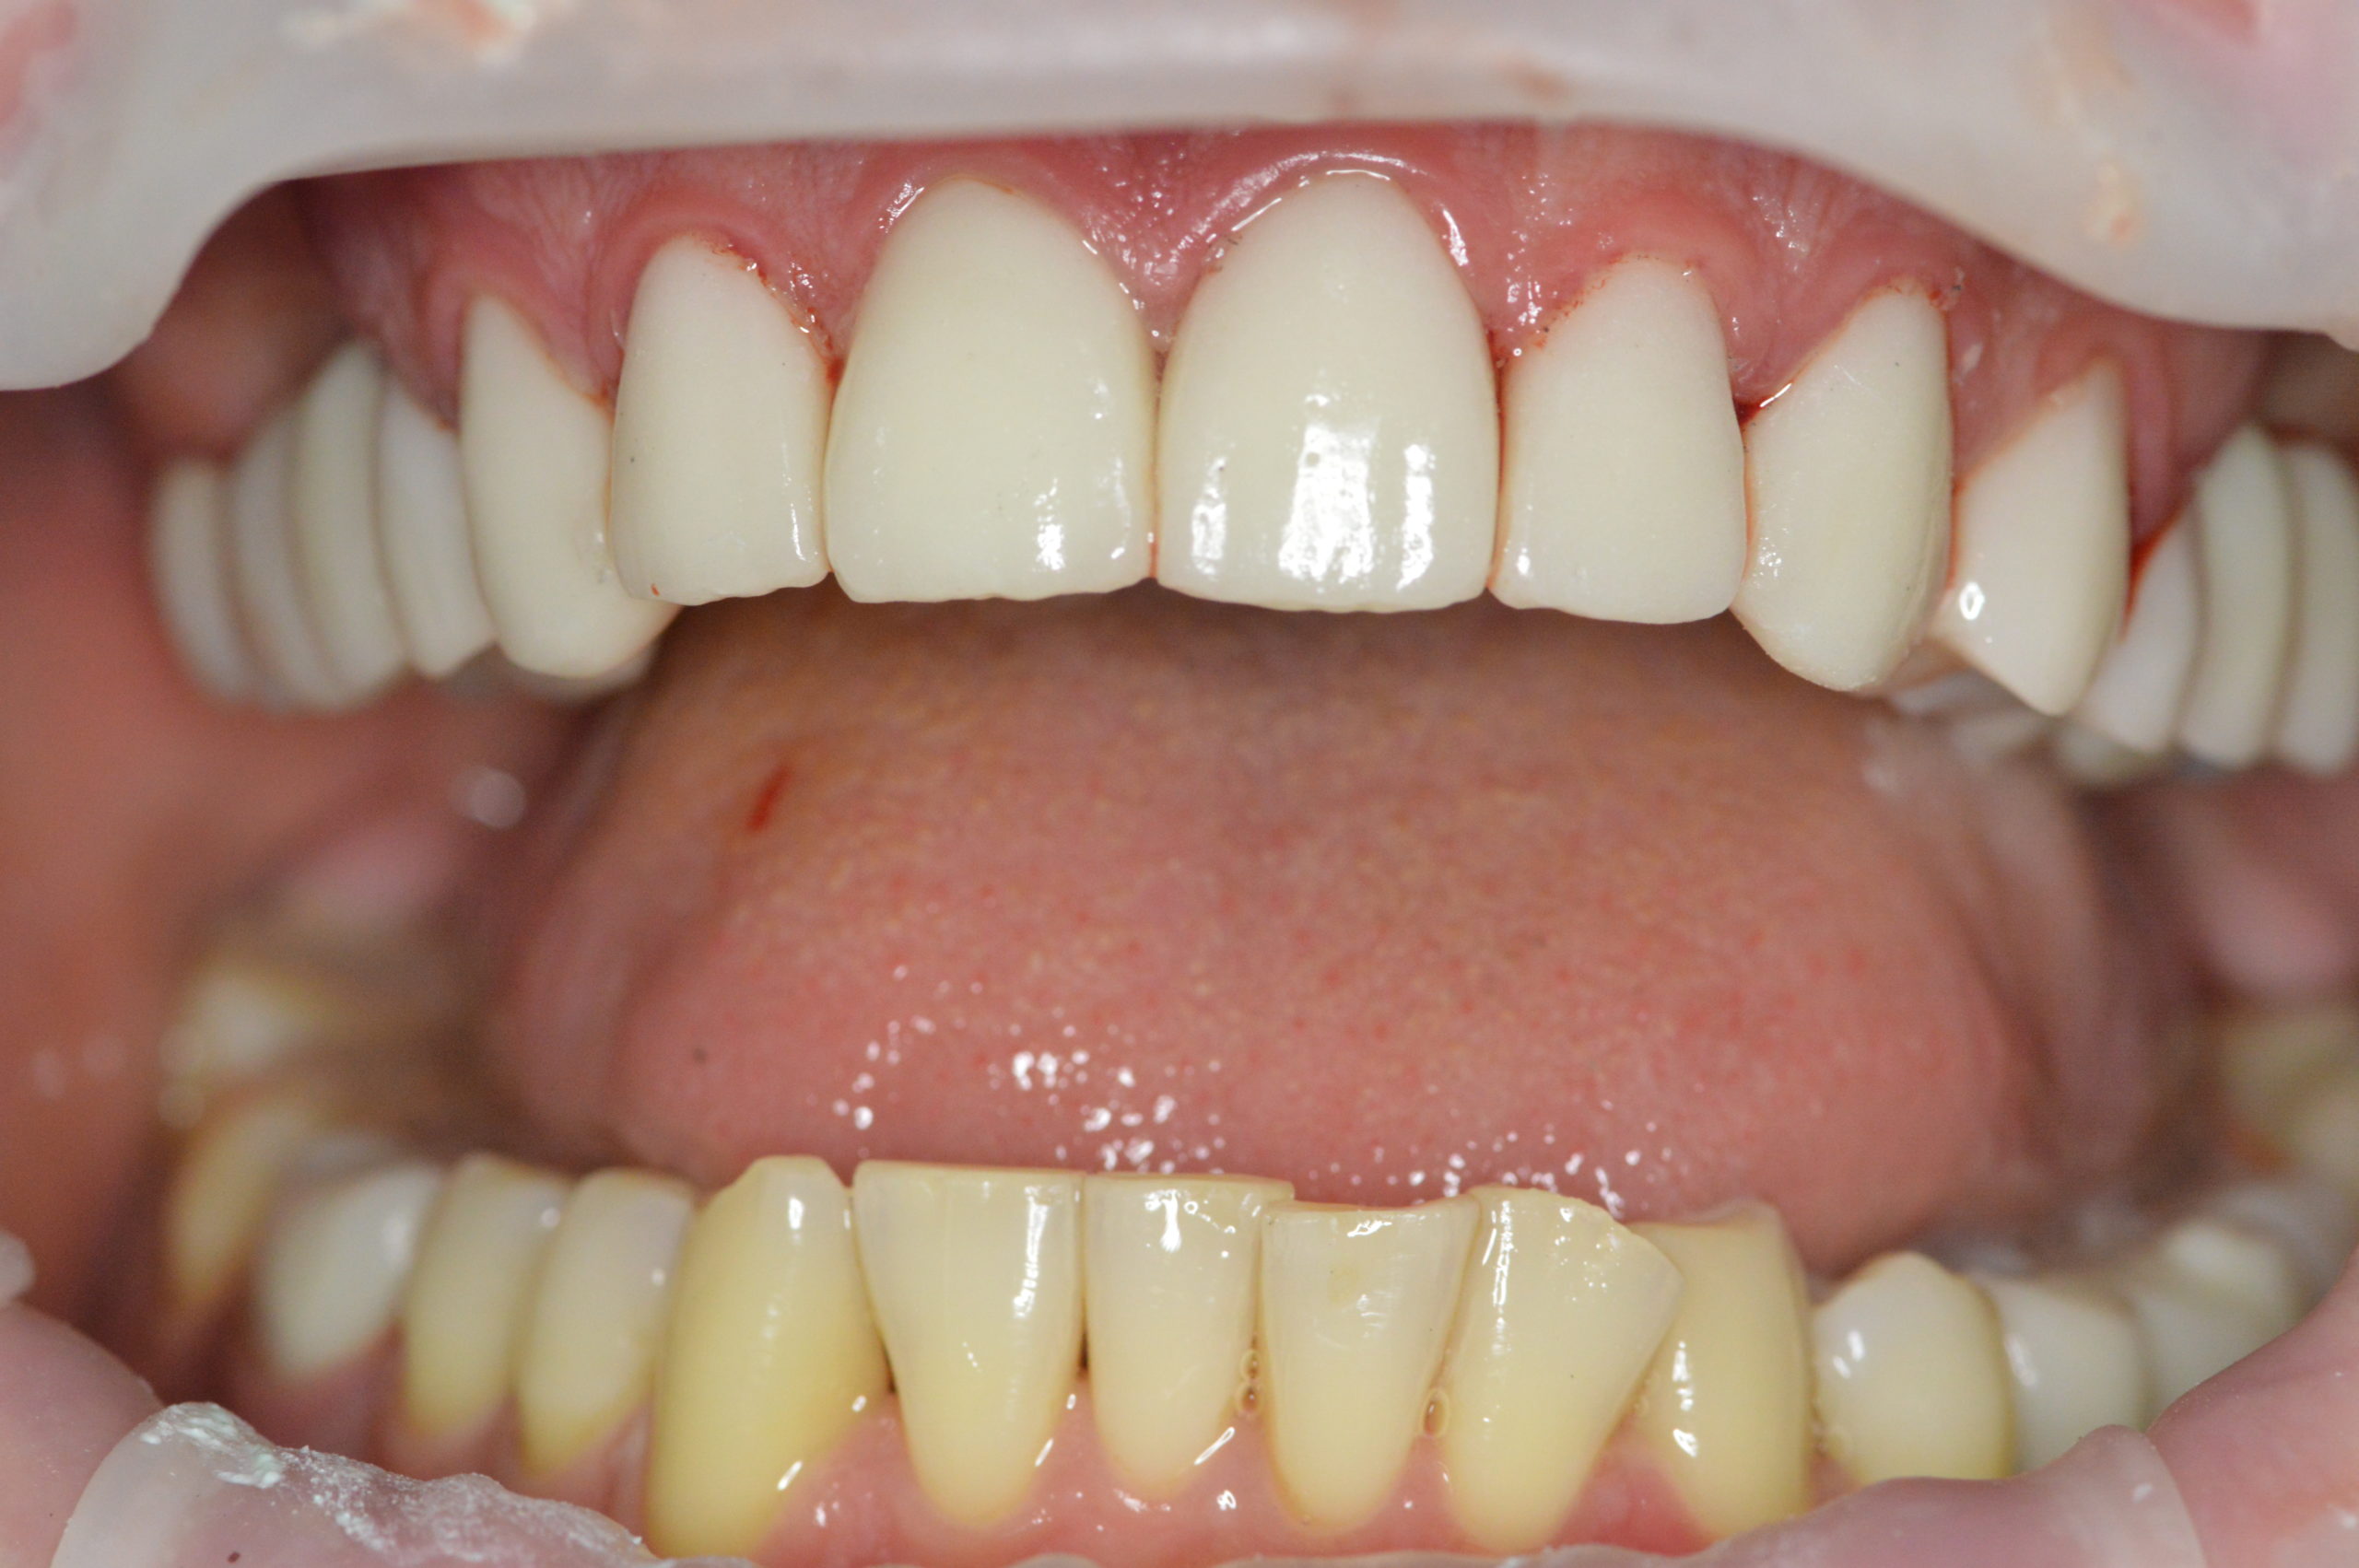

3,5 month after implantation Mr. Peter returned to our dental clinic to continue his treatment with four re-root canal procedures. Doctor decided to gave the implants more time for healing so patient returned in 2 months to get his front natural teeth reshaped and get impressions for his future implant crowns and zirconium dental crowns.

After next visit Mr. Peter left our clinic with this beautiful and natural looking smile. His upper jaw was fully reconstructed using dental implants in combination with dental crowns. Lower jaw was treated with 2 dental implants and two zirconium dental crowns.

Photo AFTER treatment with dental implants and dental crowns

Peter continues to visit our clinic to get treatment for his lower teeth. We already done 3 fillings and one root canal treatment. We are happy that we could help Peter achieve good looking and healthy smile.